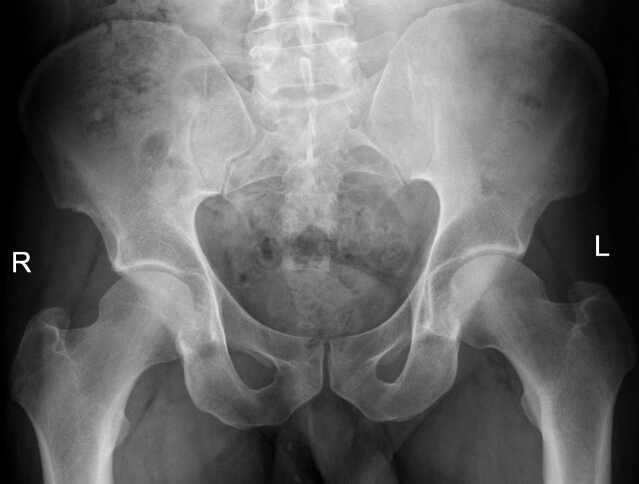

What is the diagnosis? What makes you think so?

Reflex sympathetic dystrophy

there is pretty severe demineralization and the joint spaces are good